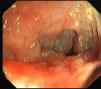

A 38-year-old man with a 20-year history of Crohn's disease presented with weight loss, abdominal distention and vomiting. He had been medicated from diagnosis with 5-aminosalicylic acid and later with azathioprine, which he intentionally stopped 2 years later. His last colonoscopy, dating 5 years before, revealed severe ulceration in the ascending and sigmoid colon. On physical examination the patient was severely emaciated. His abdomen was distended, non-tender, and showed markedly reduced bowel sounds (Fig. 1). His vital signs were normal. Laboratory tests showed mild anemia (12.7g/dL) and C-reactive protein (22mg/L), with normal serum electrolytes. Upright abdominal X-ray showed severely distended bowel loops (Fig. 2), later confirmed by abdominal computed tomography. These findings raised our suspicion for the presence of megacolon. As the patient did not presence signs of systemic toxicity we adopted a conservative approach with intravenous steroids, antibiotics, fluid support, daily abdominal X-ray and evaluation by a dedicated surgeon. On the third day of admission, a colonoscopy was performed showing an ulcerated stricture in the terminal ileum that did not allow passage of the endoscope (Fig. 3). The colon showed no signs of active inflammation. Unexpectedly, MRI-enterography showed severe distention (up to 8cm) of a wide segment of the small bowel proximal to a long stricture. The large bowel appeared not to be significantly distended (Fig. 4). The anatomopathologic examination of the small bowel biopsies showed severe transmural inflammation and architectural distortion compatible with Crohn's Disease. There were also multiple nuclear and cytoplasmic inclusions compatible with cytomegalovirus (CMV) infection. As there was suggestion that the stricture could partially be inflammatory and that the patient might benefit from medical therapy, he was started on ganciclovir and Infliximab. Unfortunately, by the 14th week of therapy there was no significant improvement. Due to progressive weight loss, the patient was scheduled for surgery. Examination of the resection specimen confirmed the long 11cm stricture with severe distention of both the small bowel (11cm) and ascending colon (9.5cm).